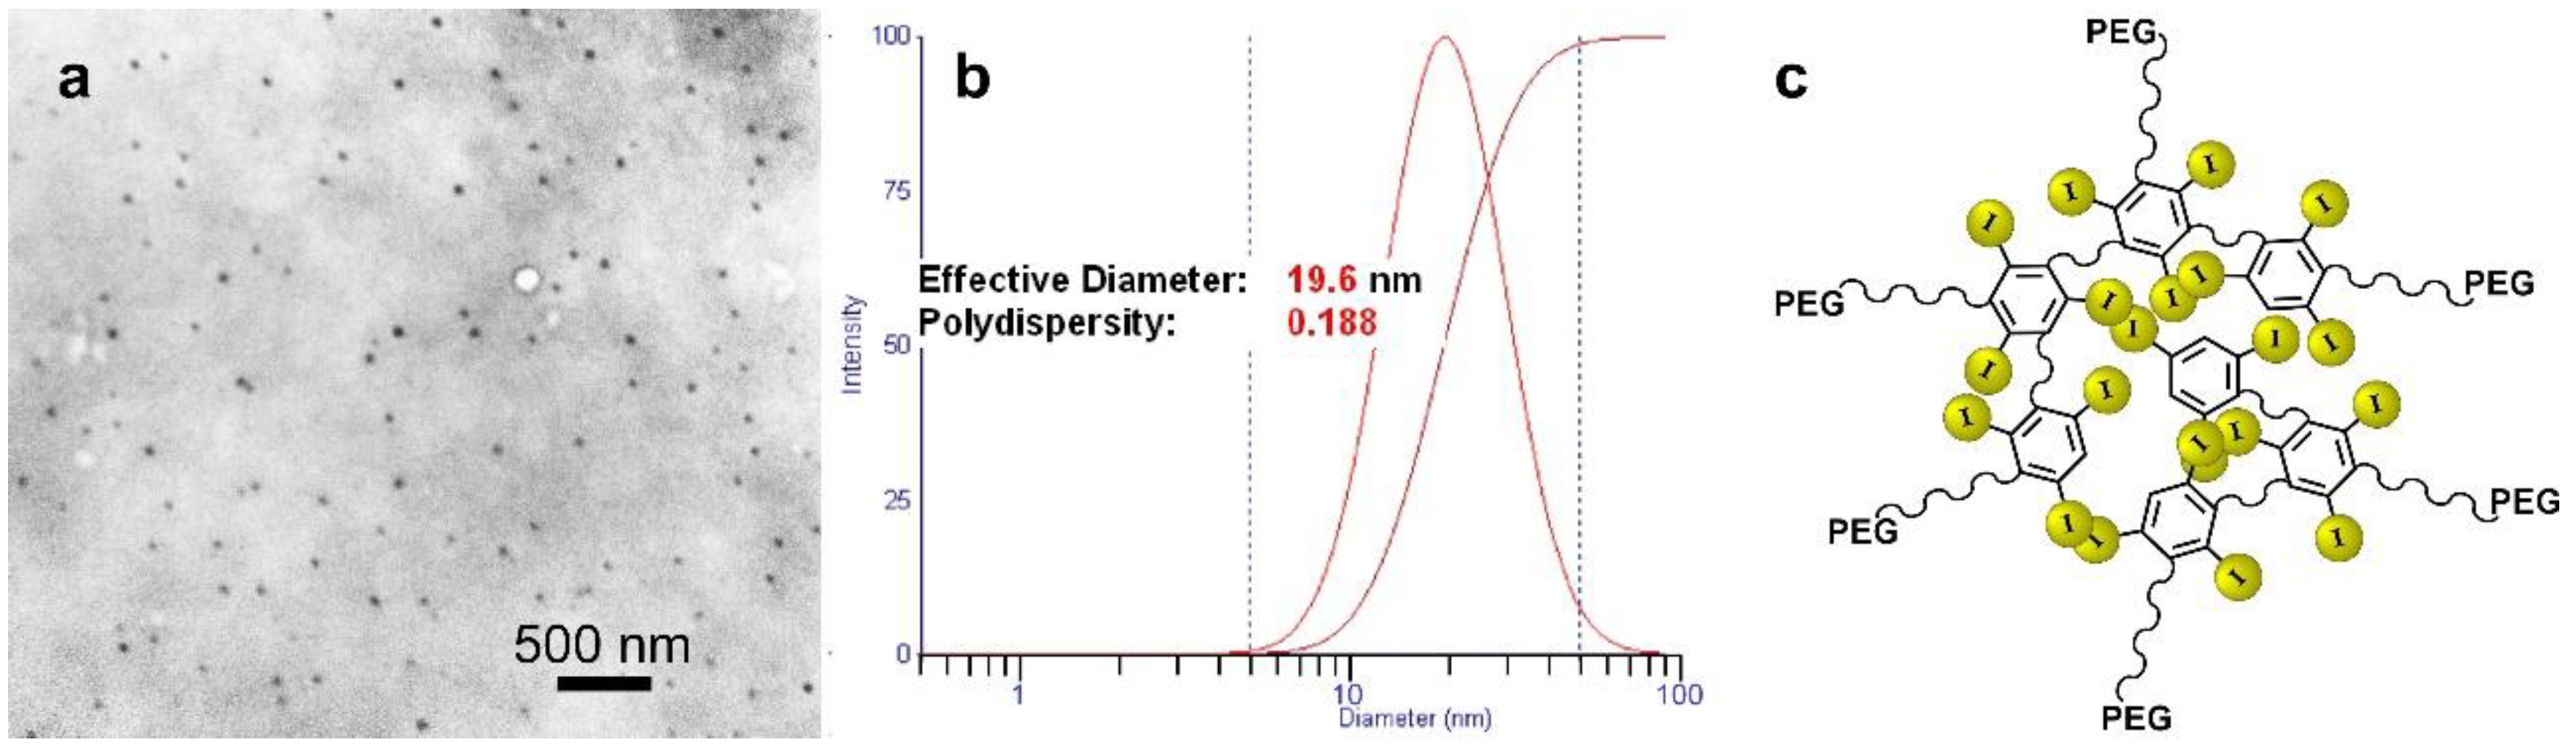

1.4. Iodine Nanoparticle Imaging

3.1.2. Physicochemical Characterization